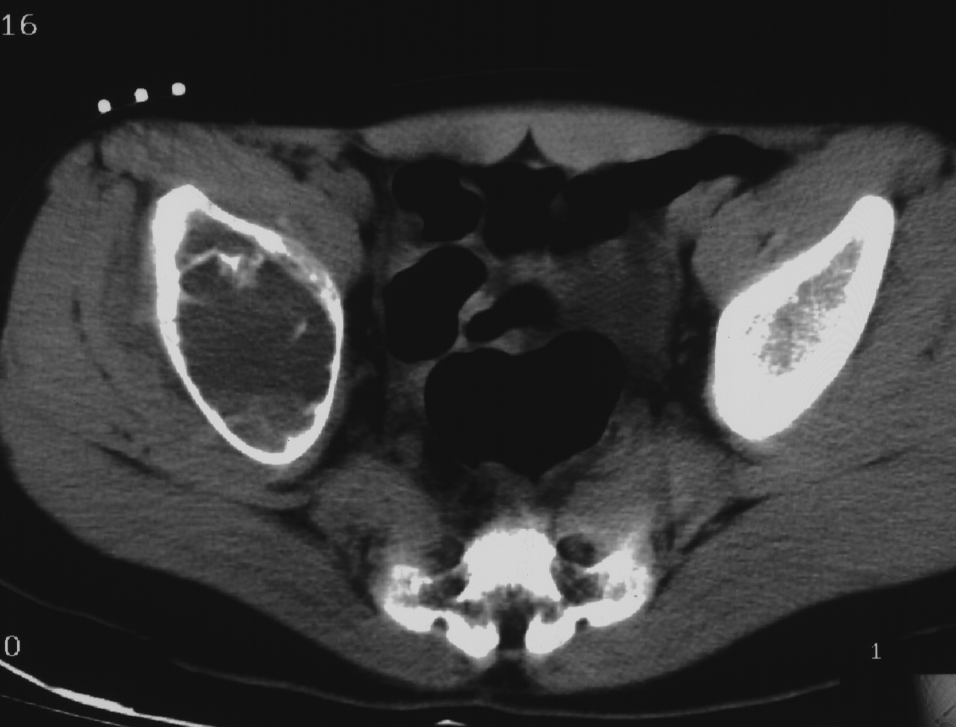

肿瘤对软骨的破坏

肿瘤对骨骺板和关节软骨的破坏是对骨破坏的继续。缺乏血管的骨骺板对恶性肿瘤有抵抗作用,骨骺板可暂时阻止肿瘤的蔓延,但当肿瘤进一步发展时, 骨骺板亦可被破坏,X 线平片或 CT 可表现为先期钙化带密度减低、中断或消失。MRI 可显示肿瘤从干骺端跨越骨骺板侵犯骨骺(图 15、图 16)。肿瘤突破关节软骨向关节腔发展时, 可表现为关节面破坏、塌陷(图 17), 关节腔内出现软组织肿块。少数良性骨肿瘤如软骨母细胞瘤, 亦可超越骺板向两侧发展或突入关节腔内, 此为肿瘤膨胀生长所致, 而非浸润性破坏。

图 16.骨骺板破坏:骨肉瘤